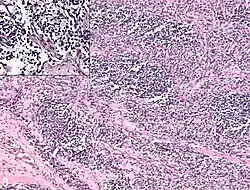

It is generally considered to be a disease of childhood, as the vast majority of cases occur in those below the age of 18. It is commonly described as one of the small-blue-round-cell tumors of childhood due to its appearance on an H&E stain.[4] Despite being relatively rare, it accounts for approximately 40% of all recorded soft-tissue sarcomas.[5][6][7]

Rhabdomyosarcoma is often difficult to diagnose due to its similarities to other cancers and varying levels of differentiation. It is loosely classified as one of the small-blue-round-cell tumors due to its appearance on an H&E stain. Other cancers that share this classification include neuroblastoma, Ewing sarcoma, and lymphoma, and a diagnosis of RMS requires confident elimination of these morphologically similar diseases.[14] The defining diagnostic trait for RMS is confirmation of malignant skeletal muscle differentiation with myogenesis (presenting as a plump, pink cytoplasm) under light microscopy.[5] Cross striations may or may not be present. Accurate diagnosis is usually accomplished through immunohistochemical staining for muscle-specific proteins such as myogenin, muscle-specific actin, desmin, D-myosin, and myoD1.[25][34][35] Myogenin, in particular, has been shown to be highly specific to RMS,[36] although the diagnostic significance of each protein marker may vary depending on the type and location of the malignant cells. The alveolar type of RMS tends to have stronger muscle-specific protein staining. Electron microscopy may also aid in diagnosis, with the presence of actin and myosin or Z bands pointing to a positive diagnosis of RMS.[5][34] Classification into types and subtypes is accomplished through further analysis of cellular morphology (alveolar spacings, presence of cambium layer, aneuploidy, etc.) as well as genetic sequencing of tumor cells. Some genetic markers, such as the PAX3-FKHR fusion gene expression in alveolar RMS, can aid in diagnosis. Open biopsy is usually required to obtain sufficient tissue for accurate diagnosis. All findings must be considered in context, as no one trait is a definitive indicator for RMS.